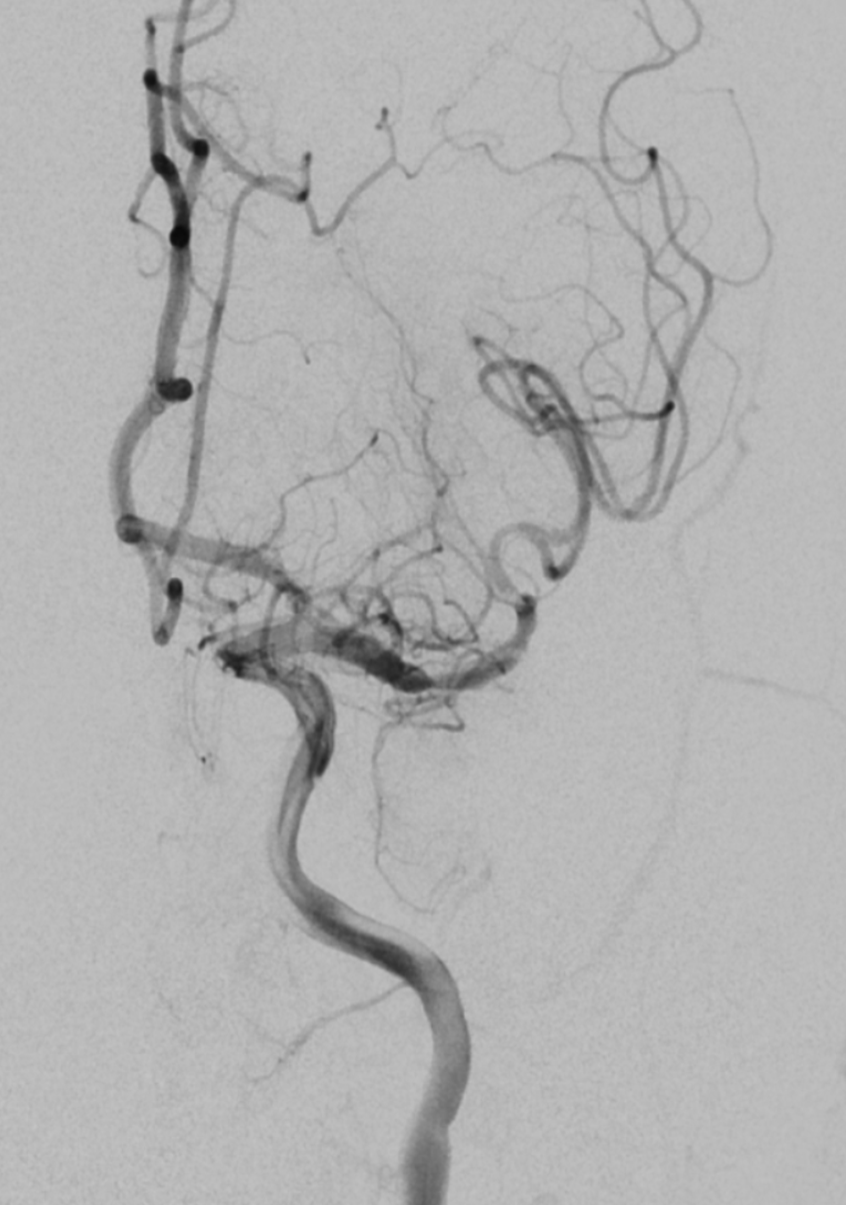

圖說:高鴻文主任在「2021台灣醫療科技展」中,以「微創介入性腦中風治療」為題在花蓮慈院攤位專家講座上分享,透過微創取栓手術,可以看出取栓前血管阻塞,取栓後血流開始暢通。

以取栓治療而言,從鼠蹊部置入導管,穿過股動脈到中大腦,醫師透過導管輕巧將抽吸或支架取栓裝置放到阻塞位置進行血栓移除,順利移除血栓後,受影響中風區域組織與細胞有可能大程度保留並得到較佳的復健效果。花蓮慈院目前執行取栓治療的醫師有影像醫學部高鴻文主任、神經影像科主任薛俊仁、神經介入診療科主任阮郁修、神經外科李建輝醫師部等醫師。

高鴻文主任舉例,一位五十二歲男性有高血壓病史病人,發病後滿分五分的力氣僅剩二分,在中大腦動脈血栓堵住情況下,經過取栓後讓血流順利通過,將大腦損傷降到最低。另一位病人是七十五歲伯伯,也是左邊中大腦動脈血栓堵住,到院時右側肢體僅剩二分力氣,口齒不清,病史包括糖尿病、高血壓、心臟病,經過取栓微創手術治療打通動脈後,讓大腦及時得到救援。